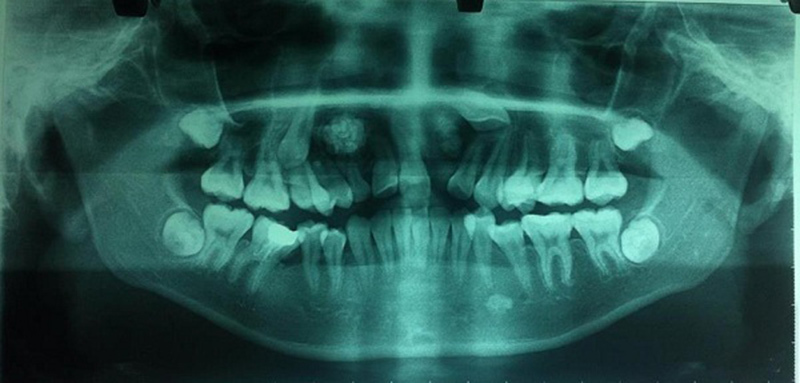

Phim Panaroma toàn cảnh răng của bệnh nhân, cho thấy u răng, răng ngầm tương ứng bên phải và bên trái trên phim |

Sau khi thăm khám và hỏi bệnh, ThS. Trung đã tư vấn cho bố mẹ bệnh nhân nên đưa con đi chụp các phim chuyên khoa để phát hiện thêm trên phim tại chỗ, phim panorama (toàn cảnh).

Kết quả phát hiện trên phim X-quang thấy bệnh nhân có u răng 2 bên và 2 răng ngầm, nên các bác sĩ đã chỉ định mổ lấy u răng và lấy răng ngầm cho cháu.